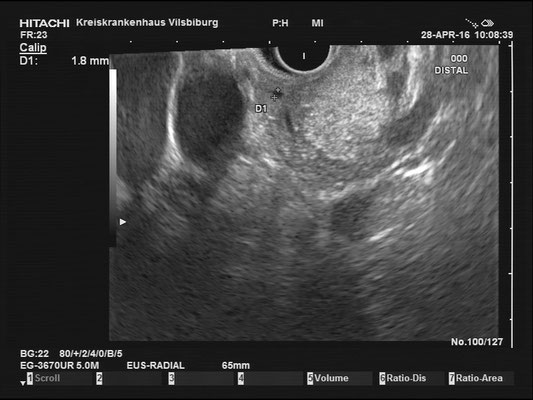

The images above depict a thorough inspection of the pancreas, as seen in an radial EUS Examination. We begin (hopefully ;) bei identifying the uncinate process between the golden V, which is formed by the aorta/V. cava and the mesenteric vessels. After spotting die usually hypoechoic ventral pancreatic root, the duodenal papilla can be identified (for a more detailed approach, please visit "Learning Endosono"). By following the splenic vein, the body and tail of the pancreas can be examined.

The most observant viewers will have noticed that not all images above depict normal findings but some abnormalities. (my bad ;)